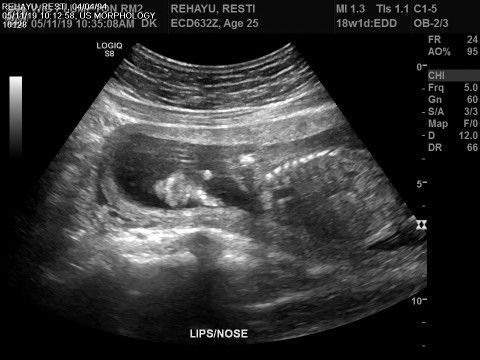

arti palate pada usg.. benarkah sumbing?

Bunda saya tinggal di sydney.aku usg pas 18 week. Di sini usgnya sama ultrasonografer bukan bidan atau dokter kandungan. Orangnya gak ngasih tahu gmana keaadaan dan kondisi janin aku.. teus di hsil usgnya ada tertulis palate. Pas aku googling artinya sumbing. Apa beneran.. ????.. bunda photo usgnya pas 18 week seperti aku juga kah?